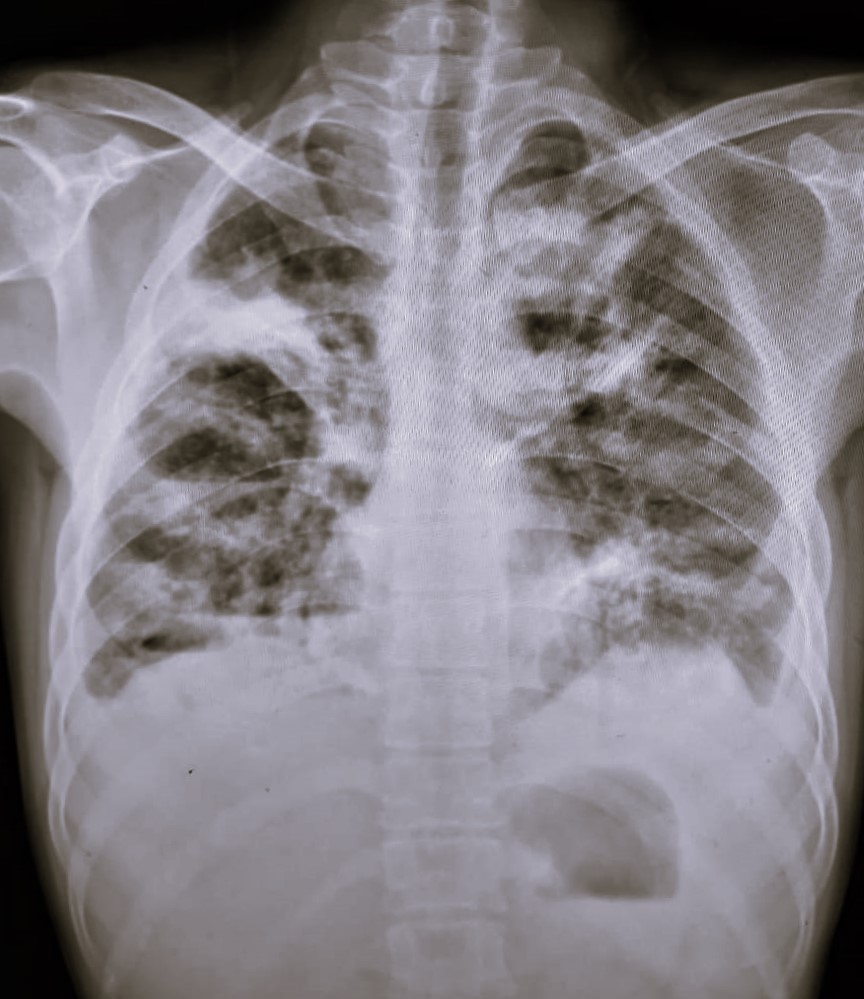

| 102 | IGGMC, Nagpur, Nagpur | P2 | 29-4370 | Prachi Bawane | Consent taken on Paper | 17 Yrs. |

Provisional Diag : PTB?

Final Diag : Active Pulmonary Tuberculosis With Tuberculi? Right Sided Pleural Effusion |

TB Case (Confirmed) | Bilateral ill Defined, No Homogenous Reticulonodular opacities, Right CP Angle Blunting | Abnormality visible on x-ray |